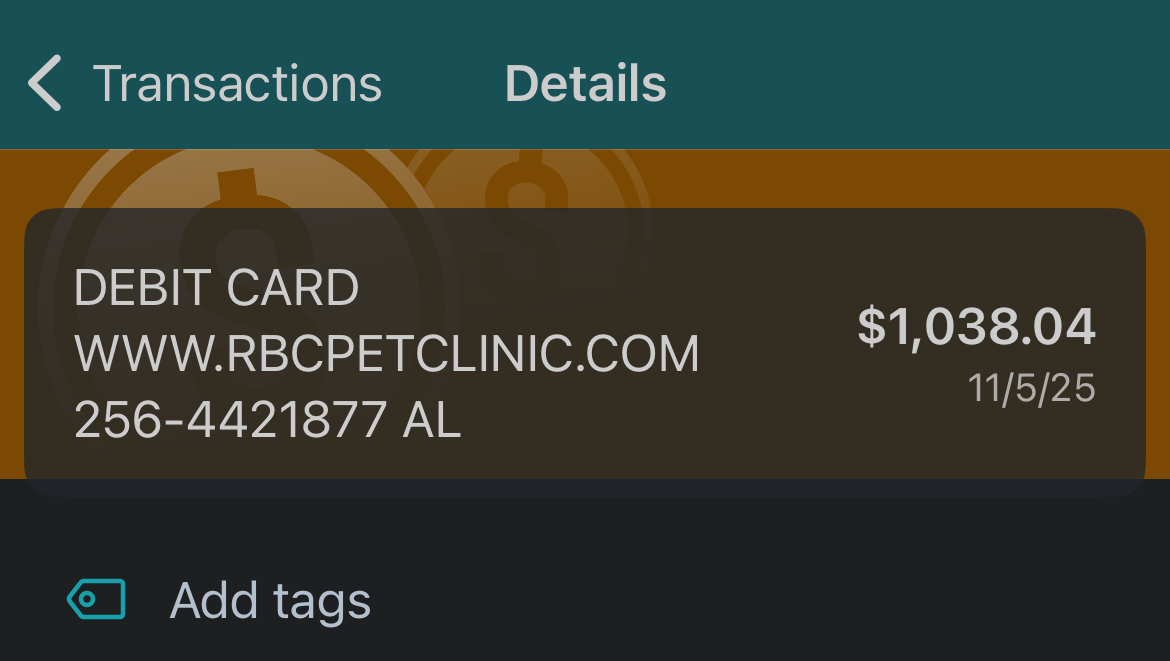

But by Wednesday, November 5th, Garbo's condition deteriorated drastically. He wasn’t moving, eating, or drinking. He seemed so weak and lethargic, it was heartbreaking to watch. I rushed him to the emergency vet at 2 a.m., and after a $300 emergency treatment, they drained his bladder, which was filled with bloodied urine. He was blocked.

As I write this, Garbo is still at the vet, and his bills are adding up fast—another $1,000 on top of everything else. That much was paid out of our own pockets.

Any donation, no matter how small, will go directly toward his treatment and surgery. We'll provide proof of payment for all vet bills and CareCredit charges, so you can see exactly where your donation is going.